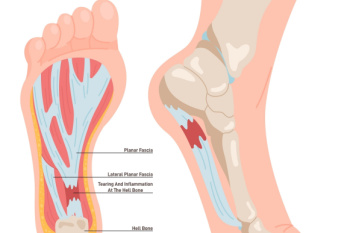

Common Foot Surgeries

Common Foot SurgeriesFoot pain can often be attributed to a number of conditions, including bunions, hammertoe, metatarsalgia, and neuromas, that require surgical intervention. Bunions are painful bony bumps on the side of the foot, caused by misalignment of the toe...